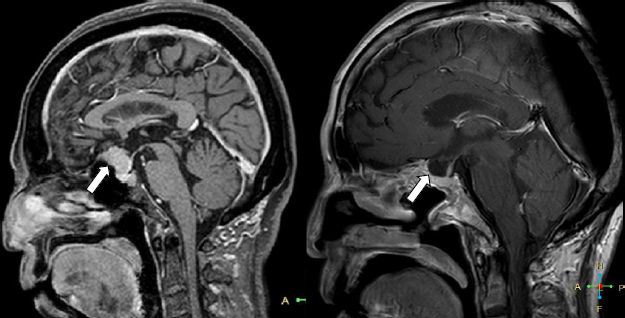

視野・視力障害で発症した鞍結節部髄膜腫です。

以前は開頭手術が選択されていましたが、最近は経鼻手術を行う事が増えています。

視神経に優しい視力の改善など良好な結果を得ています。